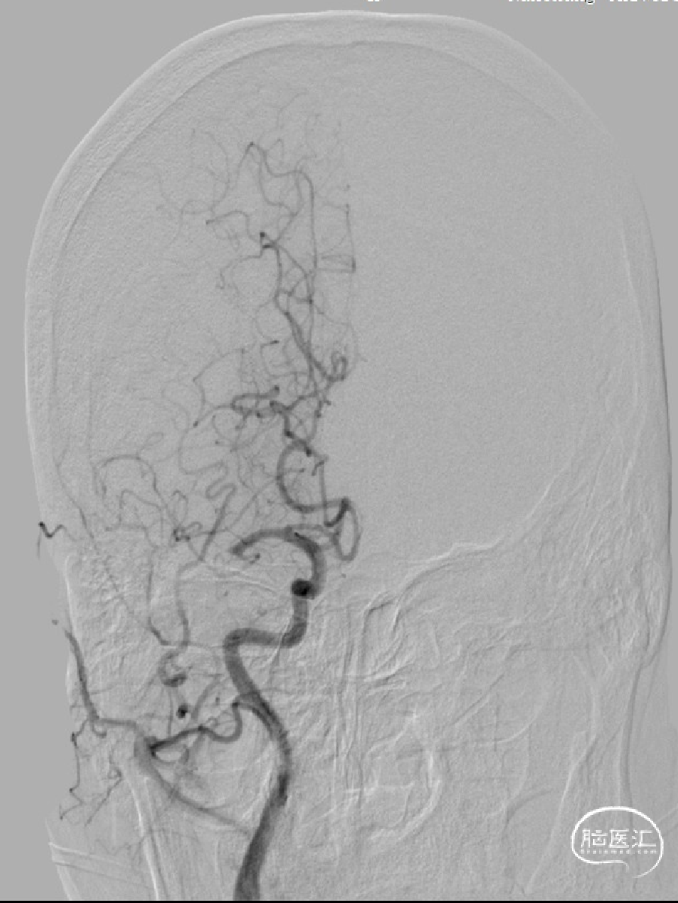

术前造影:右侧大脑中动脉M1远端不显影,断端整齐。

1. 病因评估:术前造影提示患者血管闭塞断端整齐,闭塞累及大脑中动脉M1分叉,突发起病,粥样动脉硬化性狭窄所致AIS可能性低,考虑栓塞性卒中可能性大。

将6F长鞘放置至右侧颈内动脉起始段,随后成功置入微导丝和微导管至血栓远端。在微导管的支撑下将React™ 71远端通路导管送至右侧大脑中动脉血栓近端。

React™ 71远端通路导管到位后行持续负压抽吸。抽吸后造影提示:右侧大脑中动脉血管成功再通。